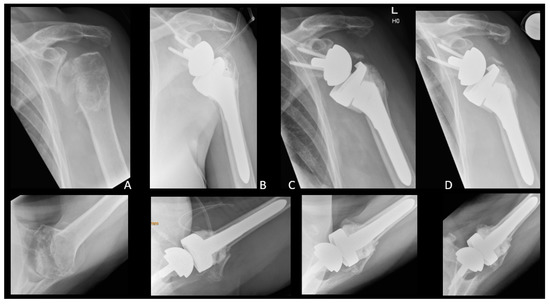

| Patient | Occurrence of GTF [Days after RTSA] | Trauma | Dislocation | Treatment | Further Dislocation of GTF | Radiological Consolidation of GTF |

|---|---|---|---|---|---|---|

| 1 | 41 | No | Slightly | Operative | No | Yes |

| 2 | 43 | No | No | Operative | Yes | Yes, after 2nd refixation |

| 3 | 391 | No | Slightly | Conservative | No | No |

| 4 | 188 | No | No | Conservative | No | No |

| 5 | 3313 | No | Yes | Conservative | No | Partial |

| 6 | 0 | No | Yes | Conservative | No | No |

| 7 | 43 | No | No | Conservative | No | Yes |

| 8 | 41 | No | Yes | Conservative | No | Yes |

| 9 | 0 | No | Yes | Operative | Yes | No |

| 10 | 3329 | No | Slightly | Conservative | No | Yes |

| 11 | 1091 | No | No | Conservative | No | Yes |

| 12 | 1580 | No | No | Operative | No | Yes |

| 13 | 43 | No | Slightly | Operative | No | No |

| 14 | 743 | No | Yes | Conservative | No | No |

| 15 | 125 | Yes | Yes | Conservative | No | No |

| 16 | 43 | No | No | Conservative | No | No |

| 17 | 340 | No | Slightly | Conservative | No | Yes |